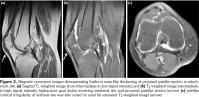

erosive changes, and swelling of olecranon bursae were seen (Figure 1). Magnetic resonance imaging showed fusiform mass-like thickening of the proximal patellar tendon, measuring 30x16 mm, with intermediate signal on T1 weighted and T2 weighted images. Edema of the tendon at insertion and patellar cortical irregularities not seen on radiograms were demonstrated (Figure 2).